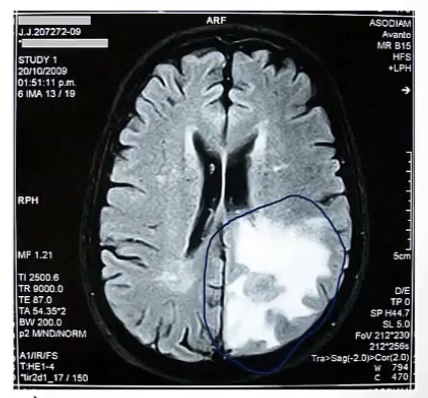

Cerebral edema

-pathophysiological cause is due to breakdown of the __

-commonly due to __ or __

-leads to __ of brain tissue

-blood brain barrier

-trauma or stroke

-swelling